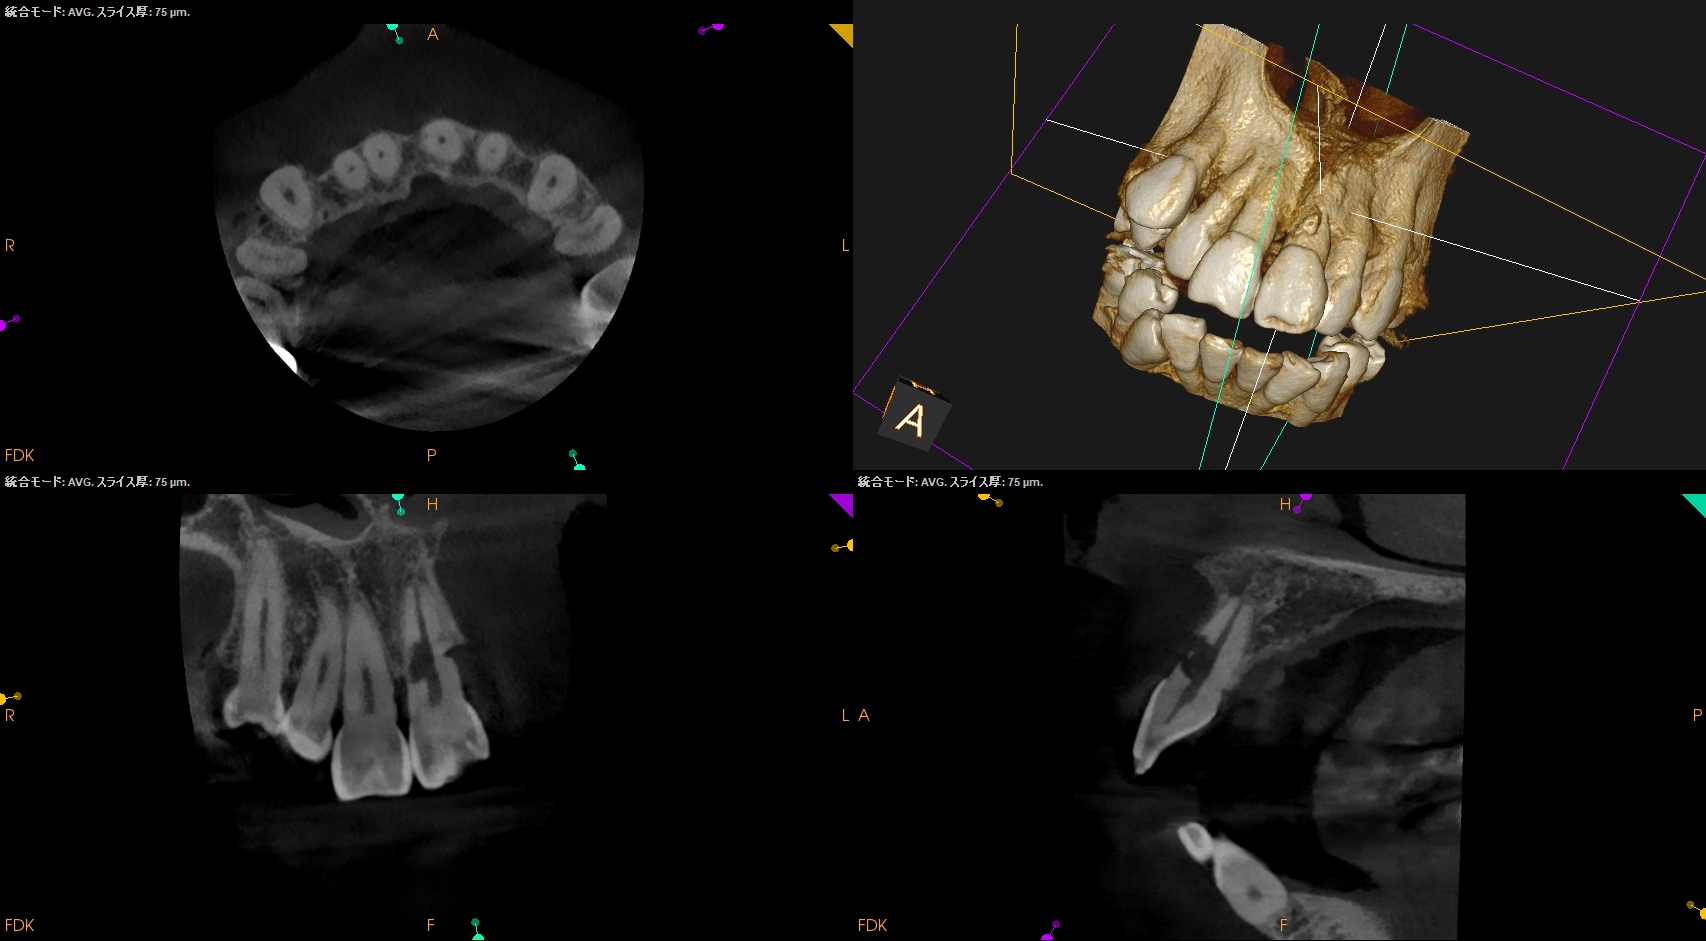

Pre-op Endo Test(2026.1.28)

#9の頬側に大きな穴がある。が、根尖病変はない。

根完成永久歯の再植後に、歯髄のRevascularizationは起きないことから本来は根管治療が必要だが、それがなされていないことからこの病態が発生したのかもあしれない。

根管治療して、支台築造して、外部吸収のRepairだが、

根管治療すると外部吸収部位が薄皮一枚で交通しているのがネック